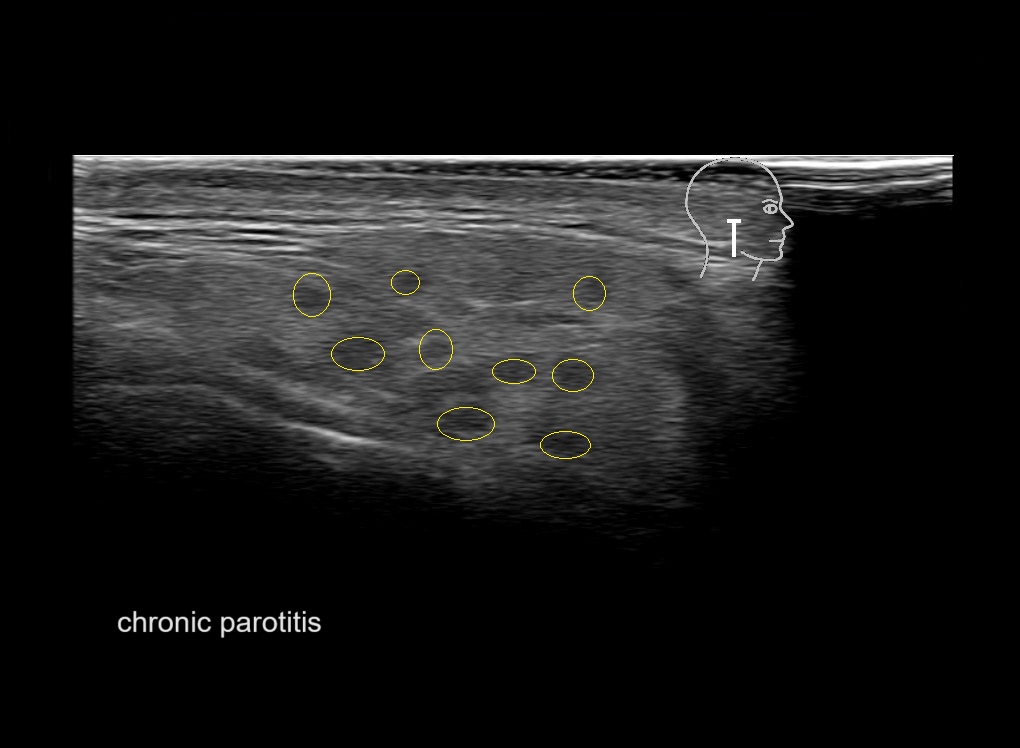

Parotid

Filler injections in the parotid gland may go unnoticed, however, inflammatory reactions and abscesses may occur. Hypervascularity can be seen with color doppler. Filler deposits are supposed to be injected into the superficial fatty layer . The space to inject into this layer may be limited. Routinely we measure a width of 2-4 millimeters with sometimes subcutaneous layers being less than one millimeter thick.

Study the first image to recognize the different layers. If you are sure about the layers, swipe to the second image to view the answer (if applicable).